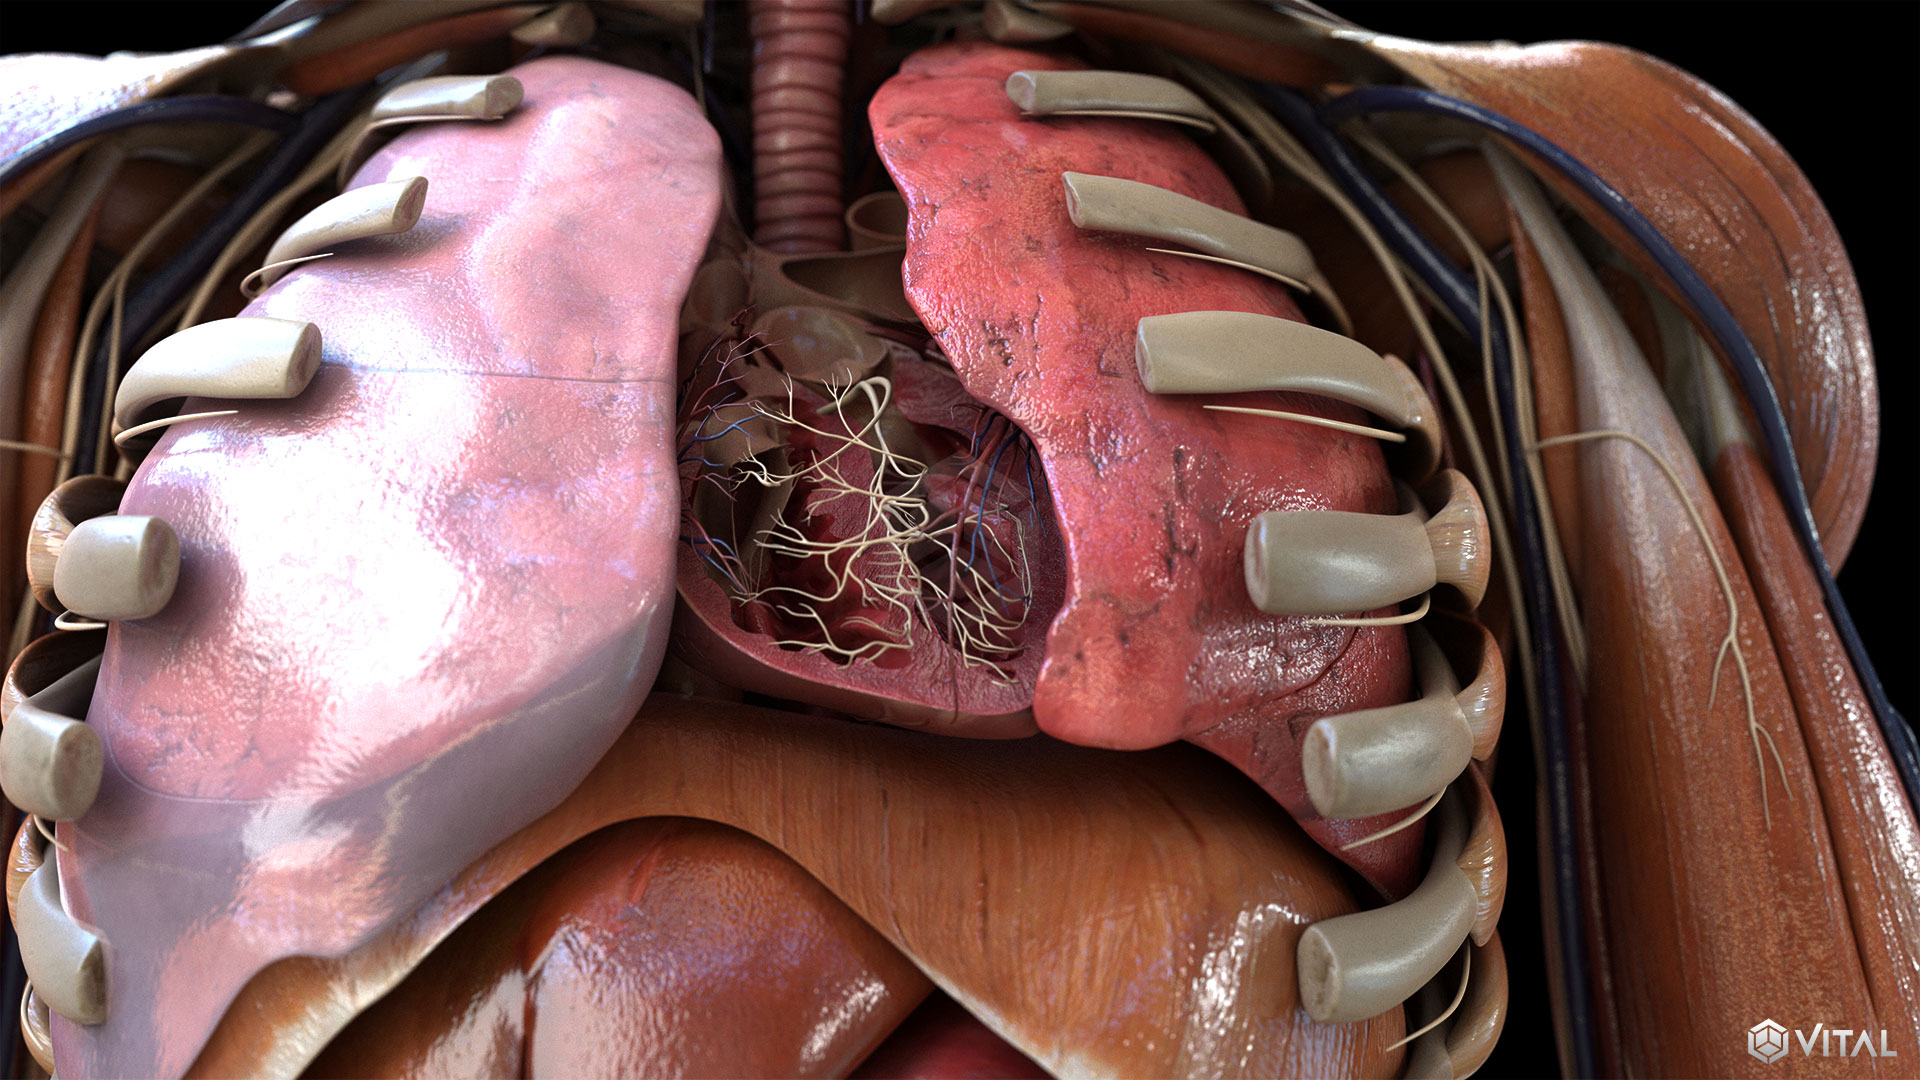

Medical

Vital and UET collaborate to support several clients throughout the medical industry. Together, we provide illustrations, animations, and trial exhibits to help depict complex anatomy and medical procedures clearly and precisely. We’re able to create an immersive, easy to understand learning experience, by combining real footage, such as captured ultrasounds, with correlating high fidelity 3D animation.